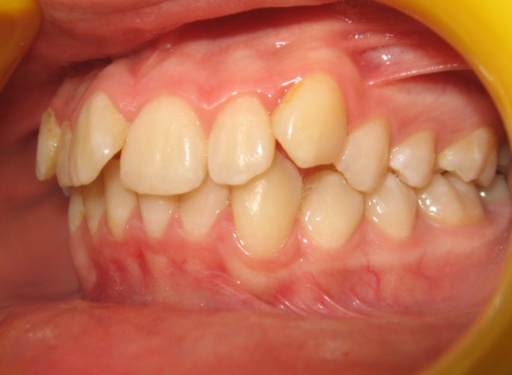

1 - Arcades dentaires avant-après

Les photos montrent un encombrement dentaire important associé à une classe II dentaire. Les extractions de prémolaires ont été décidées non seulement pour créer la place nécessaire à l’alignement, mais aussi pour corriger le décalage de classe II. Le résultat final illustre qu’un plan de traitement bien réfléchi peut répondre simultanément aux impératifs fonctionnels et esthétiques, sans compromettre l’harmonie faciale.

Le recul progressif des dents encombrées dans les espaces d’extraction créés à cet effet a été rendu possible grâce à l’utilisation de brackets autoligaturants, particulièrement efficaces pour respecter l’angulation et le torque des dents. Tous les espaces d’extraction ont été exploités pour résoudre l’encombrement, évitant ainsi tout recul des dents antérieures. L’occlusion obtenue est physiologique, en classe I canine et en classe II molaire thérapeutique.